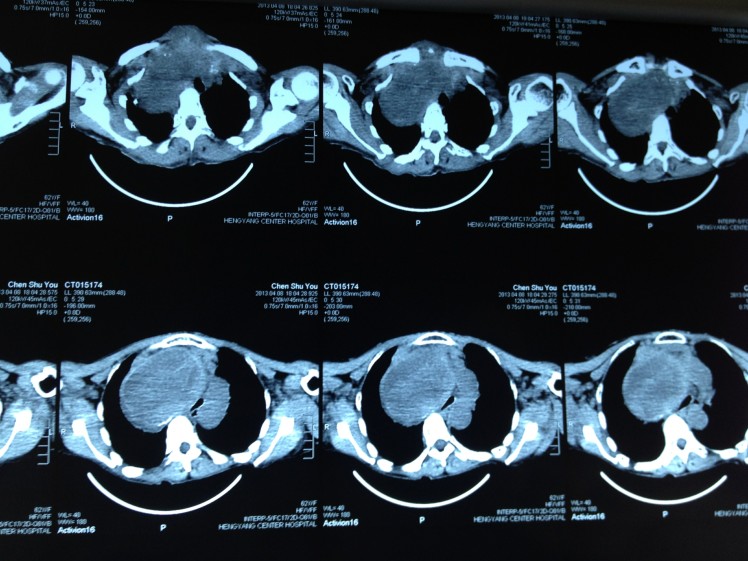

4月8日,62歲的陳阿婆因呼吸困難在家中險(xiǎn)些窒息而被家人背送我院乳甲外科就診。陳阿婆發(fā)現(xiàn)頸部雙側(cè)腫塊已有30余年,曾就診于省內(nèi)多家大型醫(yī)院,大多專家建議開(kāi)胸手術(shù),手術(shù)費(fèi)高達(dá)10余萬(wàn)元,有些醫(yī)院甚至考慮手術(shù)難度大、風(fēng)險(xiǎn)高就干脆拒收入院。我院乳甲外科尹軍主任將患者收住院后,會(huì)同醫(yī)務(wù)部組織了麻醉科、放射科、胸外科、呼吸內(nèi)科、心內(nèi)科的專家會(huì)診,進(jìn)行術(shù)前討論,制定了周密的手術(shù)方案。

手術(shù)當(dāng)日,尹軍主任采用沿頸部橫紋作一橫切口,分離左右舌骨下肌瓣,在保留左側(cè)甲狀腺上極一塊如蠶豆大小的正常甲狀腺組織后,對(duì)其余雙側(cè)病變部分采取切除、止血、從胸骨下方慢慢剝離的方式,最終成功將巨大甲狀腺腫瘤切除,并將軟化氣管懸吊。整個(gè)手術(shù)過(guò)程耗時(shí)三小時(shí),術(shù)中未輸血,整個(gè)甲狀旁腺、喉返神經(jīng)保護(hù)良好。術(shù)后病人恢復(fù)好,無(wú)相關(guān)并發(fā)癥,手術(shù)后7日患者康復(fù)出院。